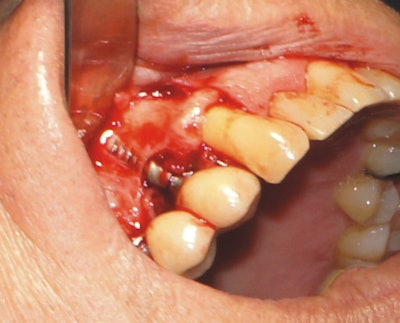

The procedure began with careful ablation of the affected area, which included hard and soft tissues, for several minutes intermittently. The implant surface of #5 was lightly brush-stroked with the laser beam and then the bony defect was forcefully ablated. Laser application was continued until the site was clean and visually free of granulation tissue.

Because of the laser's design, fast and precise cutting was easy to achieve, as ablation only requires adding more (for hard tissue) or less (for soft tissue) pressure to its variable-speed foot pedal. Additionally, the 9.3-µm wavelength allowed for simple removal of the edematous tissue while maintaining the integrity of the tooth. Healthy bone remained, and the implant surface was not significantly altered. The water mist permitted thorough cleaning of the site visually, which aided in predictability.